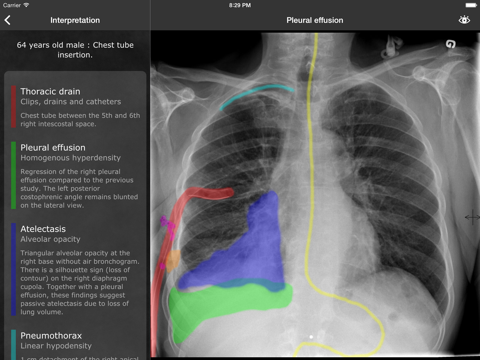

Dental Study

| 10 | Dental Study | 14 | 3.9 ⭐ |